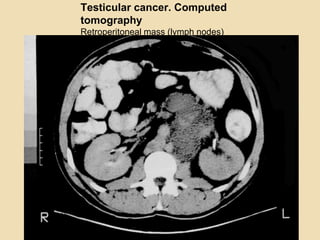

Testicular cancer. Computed

tomography

Retroperitoneal mass (lymph nodes)